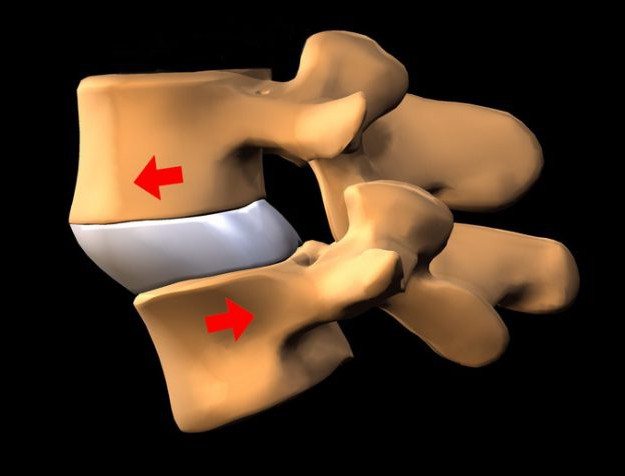

Спондилолистез — форма патологического поражения позвоночной системы, при которой происходит смещение или соскальзывание близлежащих позвонков относительно друг друга.

Лечение спондилолистеза позвоночника, по описанию различных медицинских источников, можно смело отнести к категории клинических патологий поясничного отдела, так как в 85 % случаев поражение определяют, как спондилолистез L5 – S1 позвонков, около 10% случаев соскальзывания фиксируется на уровне L4 и L5, спондилолистез L3 и L4 позвонков относят к 5% патологической аномалии.

В редких случаях определяются патологии шейного или пояснично-крестцового отдела позвоночника.